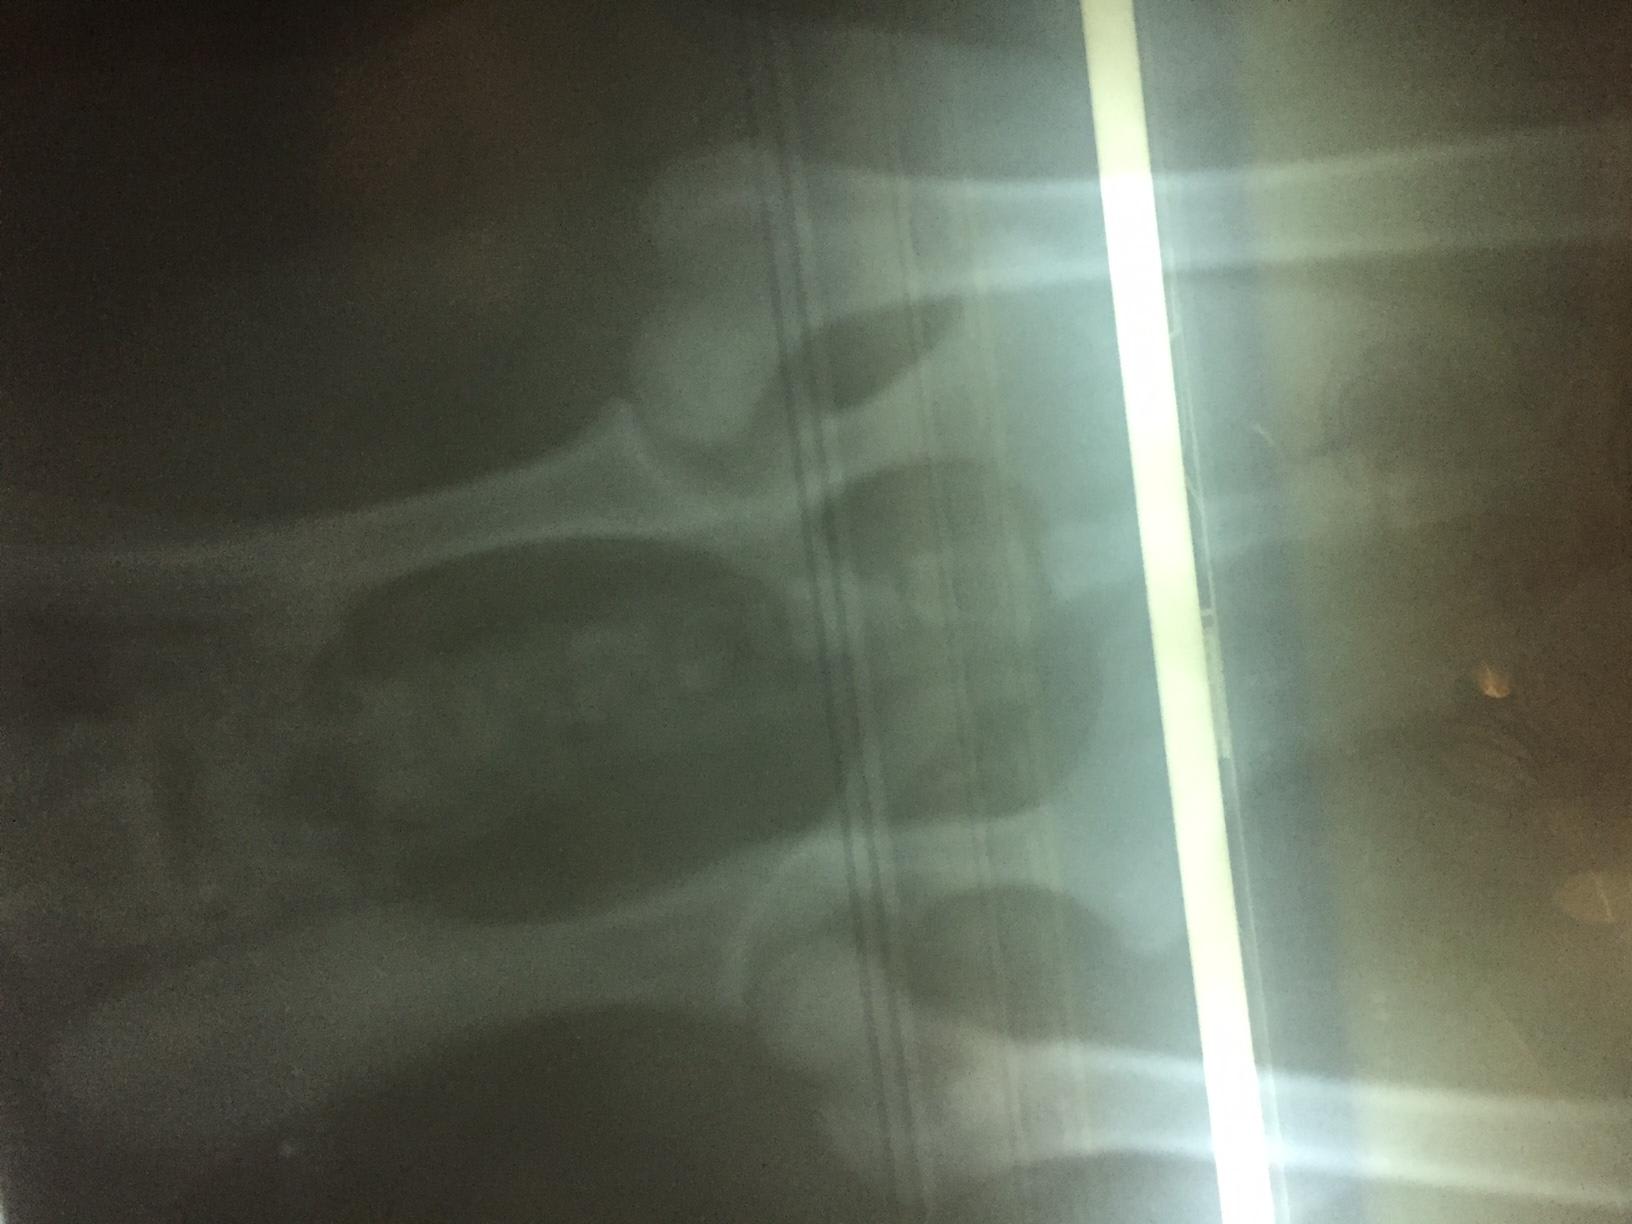

I showed the X-Ray to 2 doctors. One Doctor said that the position of limbs are not good & this issue may be there for life or may be not & the other doctor said that X-Ray hasn't been positioned properly so it looks like joints are sublimated, also he is a pup, so suggested to continue with HD tablets & Pet joint for a month. She also asked me not to overthink until Browny is not able to walk or move. Need one more opinion. Need to understand what does the X-Ray show..

I agree with the doctor who said the x-rays were not positioned properly. In order to obtain really diagnostic quality hip x-rays, the patience should be fully sedated. Without being able to bend the hips all the way downward, you simply can not obtain completely accurate results. Depending on the current clinical picture, I might possible recommend starting medication. Joint supplementation definitely can't hurt, but starting an NSAID at this early of an age is not advisable unless there is clear and obvious discomfort / inflammatory pain. Hope this helps!